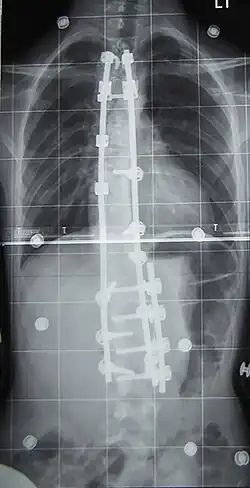

![]() Рентгеновский снимок позвоночника пациента со сколиозом с левосторонним искривлением в поясничном отделе и правосторонним искривлением в грудном отделе позвоночника. | |

Хирургическое лечение

При неуспехе бескровного консервативного лечения из-за нарушения предписанного режима ношения корсета, плохого качества изготовленного корсета или отказе от него рассматривается операция по установке металлических конструкций и аутотрансплантантов (небольших фрагментов кости таза пациента, превращённых в костную крошку) фиксирующих между собой тела позвонков, называемая «спондилодез» или «fusion»-закрепление(слияние, заваривание).

При оперативном лечении искривлённая часть позвоночника выпрямляется до определённого возможного угла при помощи металлических стержней и шурупов (т. н. транспедикулярных винтов), что ведёт к полному обездвиживанию этих отделов позвоночника. Операция при сколиозе подходит прежде всего для сильных искривлений, которые больше не могут лечиться другими методами. Оперативная фиксация может предотвратить дальнейшую прогрессию и ухудшение состояния.

Существуют два основных типа операций при сколиозе: операции с задним(дорзальным) и передним(вентральным) доступом.

Оперативный разрез при заднем доступе находится на средней линии туловища и одном из крыльев тазовой кости. Используются различные системы металлических стержней, которые крючками или шурупами (т. н. педикулярными винтами) прикрепляются к позвоночнику и затем изменяют его кривизну на больших участках. Для лучшей стабилизации всей конструкции стержни имеют поперечные соединения (мостики).